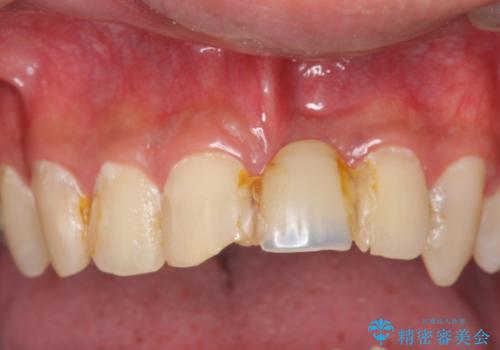

- マウスピース矯正治療に先立って、虫歯が見つかったため治療を行いました。